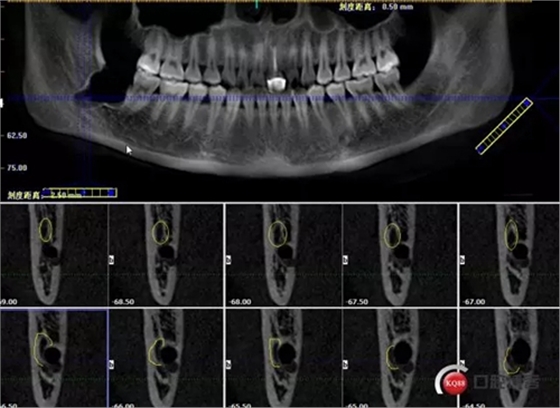

1498615723_447506.png

牙齒上1/3CT切片,神經(jīng)管在下方